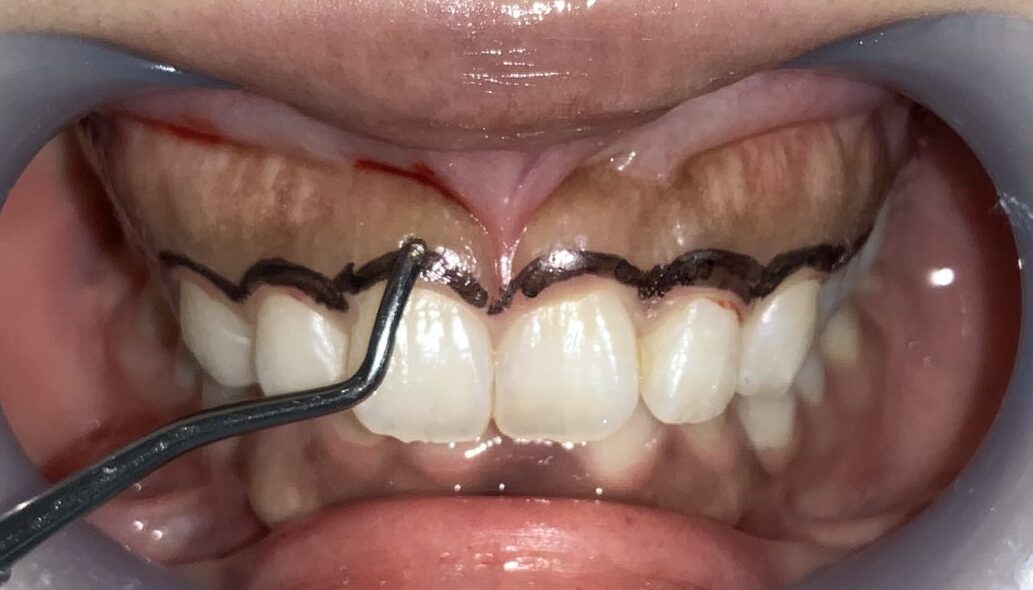

まずは歯ぐきのかぶり具合、歯ぐきの厚み、歯槽骨の状態、歯ぐきの切除範囲の検査からです。

このくらいかぶっていますから、綺麗に切除できます。

検査結果から、歯ぐきの切除範囲をマーキングして、もう一度検査データと切除範囲の間違いがないかを確認します。

切除範囲の設定は完璧です。